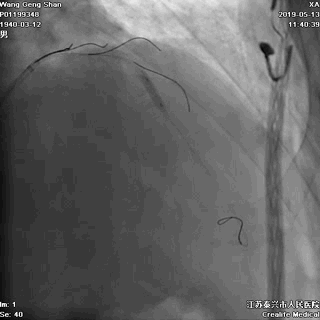

一、冠脉造影基线资料

回旋支开口狭窄90%,

中间支开口狭窄90%,

左主干尾部狭窄50%并延展至前降支近段,

前降支近段病变伴中段局限性狭窄